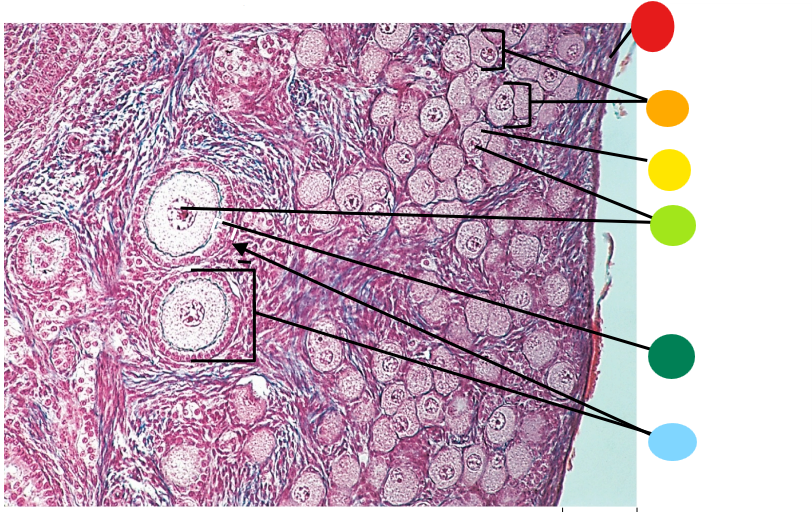

Lab H: Female reproductive histology

red

tunica albuginea

orange

primordial follicles

yellow

follicular cells

light green

primary oocyte

dark green

granulosa cells

light blue

primary follicles

what is this?

ovary